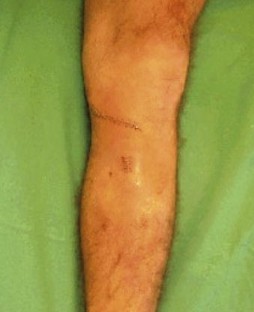

Fig. 5a, b.